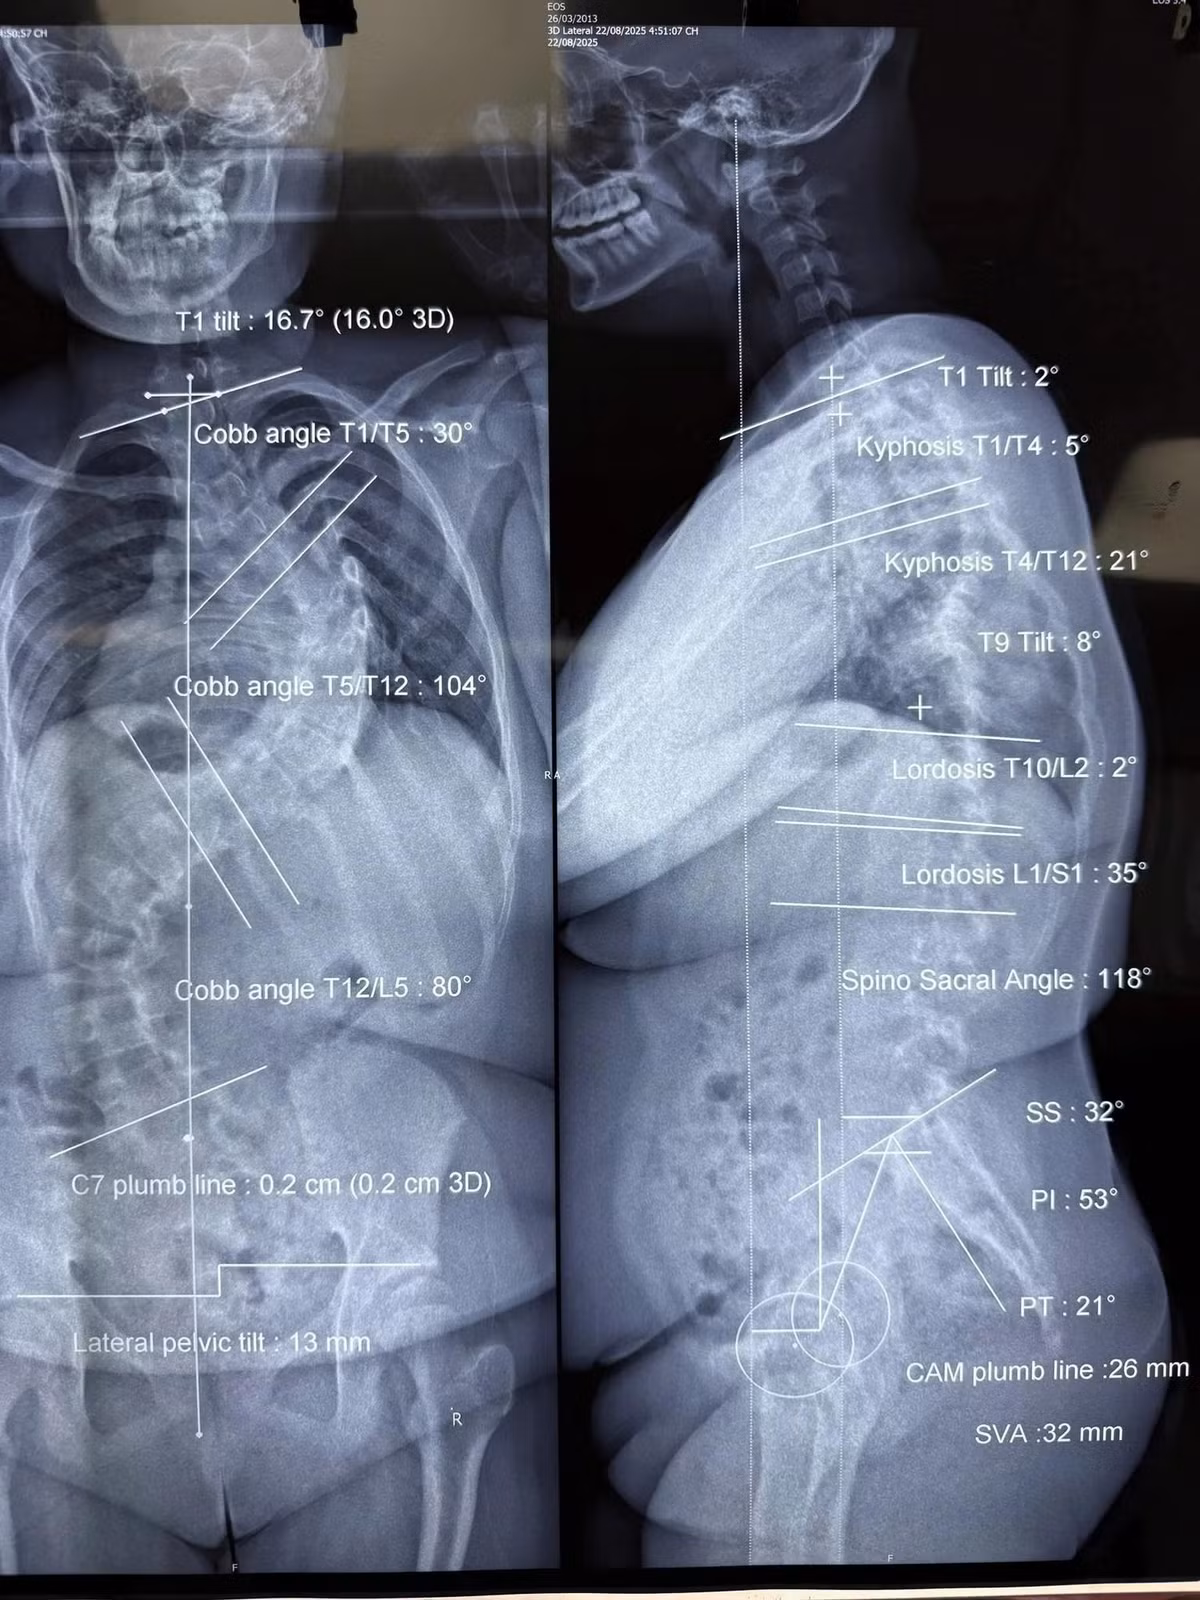

Nhiều bệnh viện trước đó đã từ chối phẫu thuật vì rủi ro gây mê vượt ngưỡng an toàn. Chỉ trong 7 tháng chờ đợi phẫu thuật, độ vẹo cột sống của L tăng nhanh từ 78 độ lên 104 độ, kéo theo đường cong thứ hai 80 độ ở vùng thắt lưng. Mẹ bé từng run rẩy không dám đặt bút ký giấy cam kết phẫu thuật.

Tình trạng gù và cong vẹo cột sống của bệnh nhi - Ảnh BVCC

Khác với bé L., thách thức của bé Y.T (13 tuổi) đến từ thể trạng quá yếu. Bé chỉ nặng 28 kg do suy dinh dưỡng nặng, mắc hội chứng hạn chế hô hấp, cột sống cong đến 128 độ và gù 108 độ khiến lồng ngực bị chèn ép liên tục, chỉ có thể nằm sấp khi ngủ.

Hình ảnh cột sống cong vẹo trên phim chụp của các bệnh nhi - Ảnh BVCC